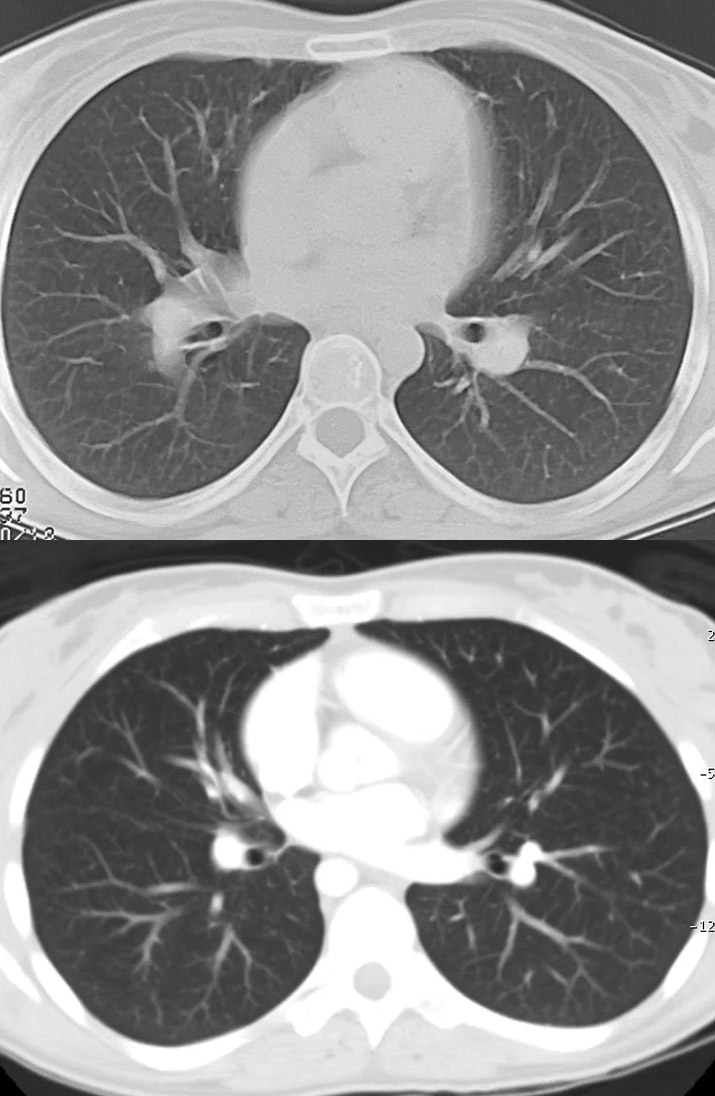

◂Chest CT for Internal Medicine Residents